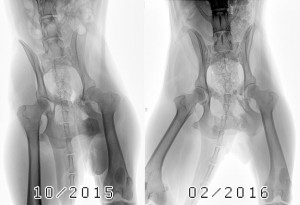

R. Scharwey | Haflinger Wallach

Behandlungsmöglichkeit Equins Cushing Syndrom | Symptomatik: Seit drei Jahren zum Teil unerklärliche, wechselnde Lahmheiten…